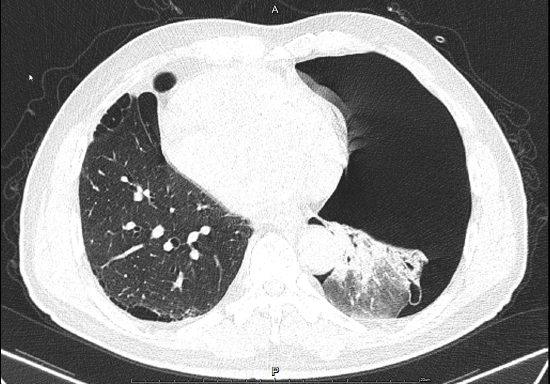

胸部ct提示双肺多发巨大肺大泡,左侧大量气胸